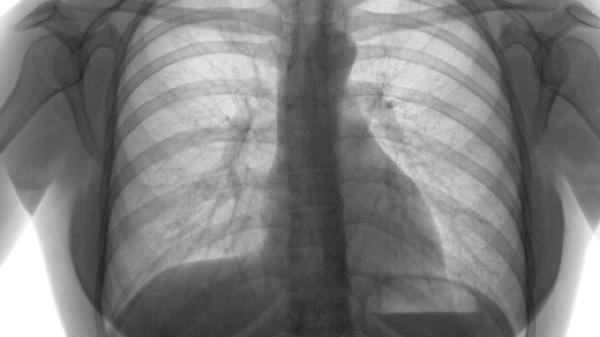

肺气肿的本质是肺泡结构破坏,属于非感染性病理改变。其核心机制为蛋白酶与抗蛋白酶失衡导致肺组织损伤,与病毒、细菌等病原体无关,因此不会通过飞沫或接触传播。

患者表现为进行性呼吸困难、咳嗽咳痰等症状,但无发热、脓痰等感染征象。儿童若出现类似症状需考虑哮喘、支气管炎等疾病,而非被传染肺气肿。

传染性呼吸道疾病如肺结核、流感等具有特定病原体和传播途径,而肺气肿是终末细支气管远端气腔永久性扩张,两者发病机制存在本质区别。